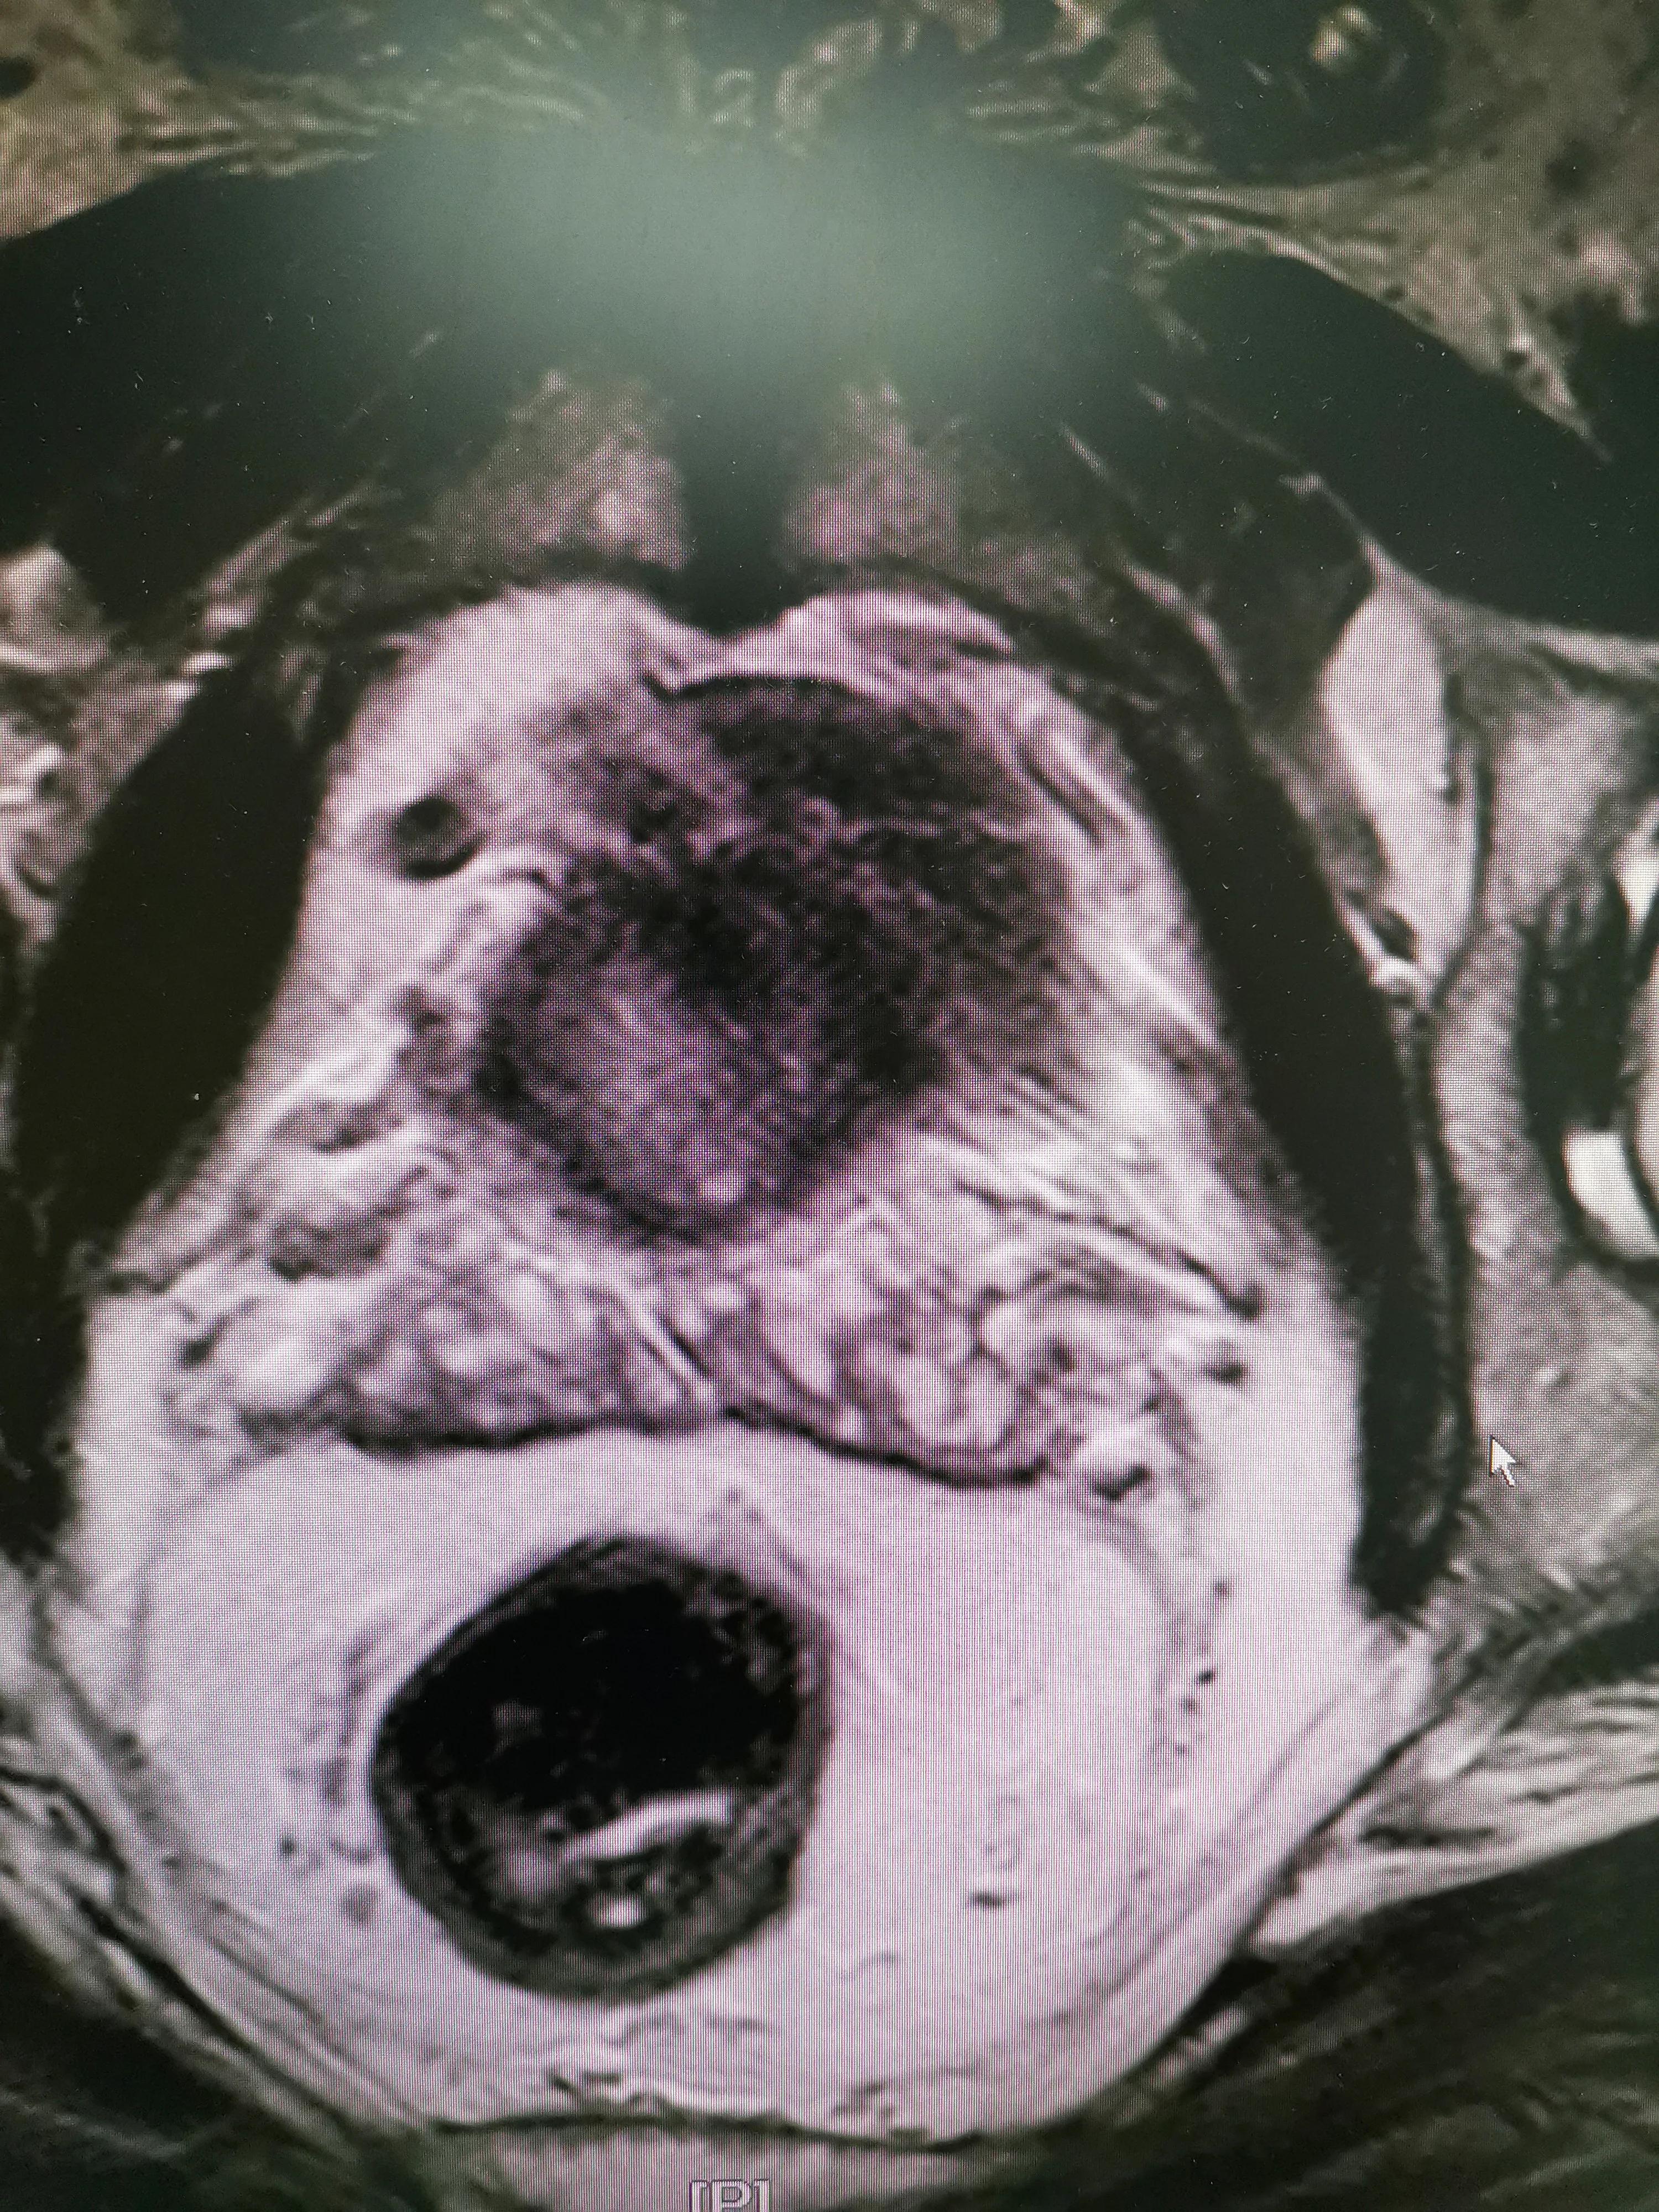

전립선 초음파 검사(특히 경직장 전립선 초음파)를 통해 전립선의 크기와 구조, 염증성 변화 여부를 정확하게 파악할 수 있으며, 종양이나 결절, 석회화 등의 유무도 확인할 수 있습니다.